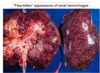

What are the 2 most common etiologies causing Acute Tubular Injury?

- Ischemia i.e., hypotension, shock, HUS, TTP, or DIC

How does the pattern of tubular damage in the PCT, PST, and ascending loop of henle seen in acute tubular injury differ between ischemic and toxic sources?

- Ischemic = patchy necrosis of these segments

- Toxic = continous necrosis of PCT and PST w/ patchy necrosis of ascending loop of henle